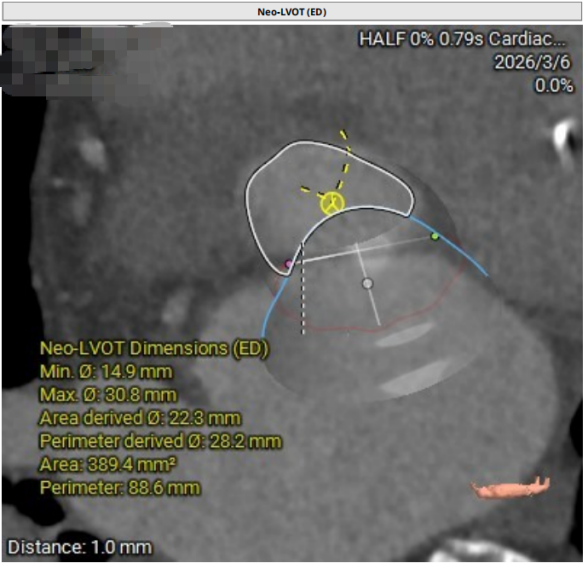

Neo-LVOT评估

05.jpg

06.jpg